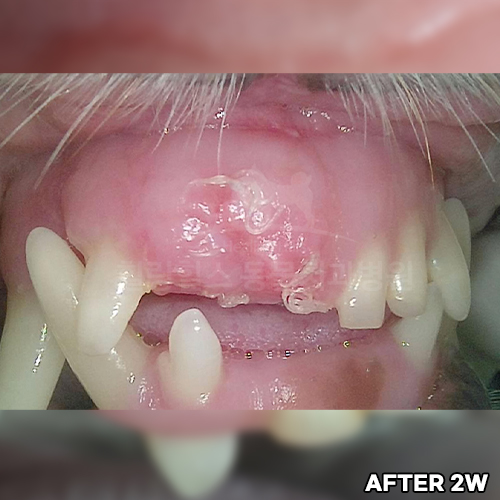

[강아지 치은종 제거 후 2주 경과]